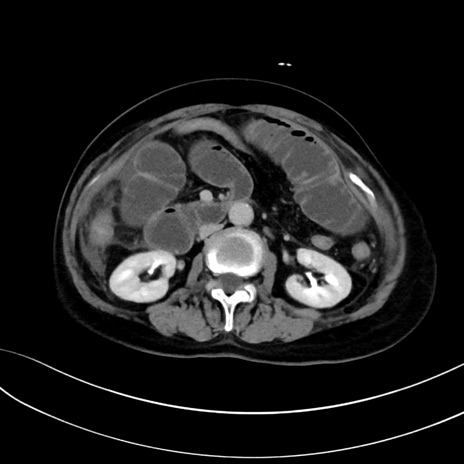

(冠状断像)1日半後